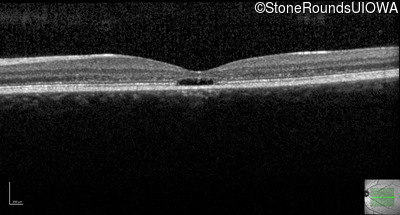

Age at visit: 17 years

OD OS

This 17 year old female first noted problems with her visual acuity around age 13 when she had trouble seeing the projector from the back of the classroom.